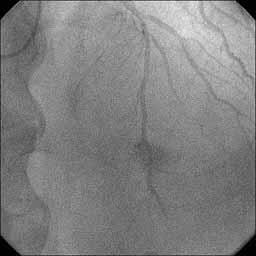

�Ǘ��72�Ώ����Brisk factor��HT, HL, DM�ł��B

��2�T�ԑO�̔��ǂƎv����Recent MI�ł��BLAD#7: total��Tristar3.0�~18?�����

�܂����B

����LCx ostium: 75%�ł��B������PCI���悤�Ǝv���̂ł����A�ǂ̂悤��strategy

���l������ł��傤���H

�����搶�̏Ǘ�ɂ��āA�k�b�w�a�ςɂ������鎡�Ð헪�́����搶�⁛���搶�Ɠ�

���Ȃ̂ŏȗ����܂��B���̏ǗႪ2�T�ԑO�̔��ǂƎv����Recent MI���Ƃ��āA�k�`

�c�̈�̃o�C�A�r���e�B�͂ǂ̂悤�ɔ��f����o�b�h�������̂��H�����_�ł̐S�@

�\�⍡��̉��P���ǂ̂悤�ɍl������̂��H�k�b�w�̋������ǂ̂悤�ɔ��f�����

�̎����Ɏ��Â��ׂ����ƍl������̂��H�E��������Ao-ostium�̕a�ς͂ǂ������

�̂��H�s���ȓ_���������낢��Ȍ�ӌ�������Ǝv���܂����A�F����ǂ̂悤�ɂ��l

���ł��傤���B